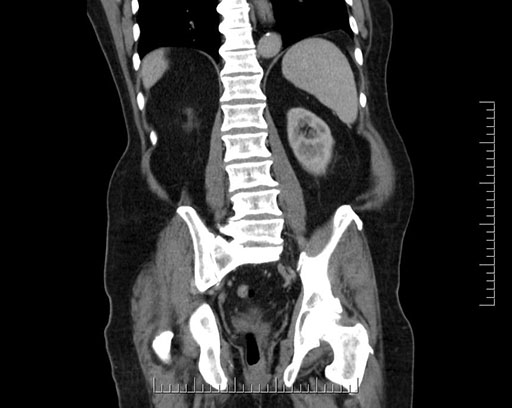

Axial - stented